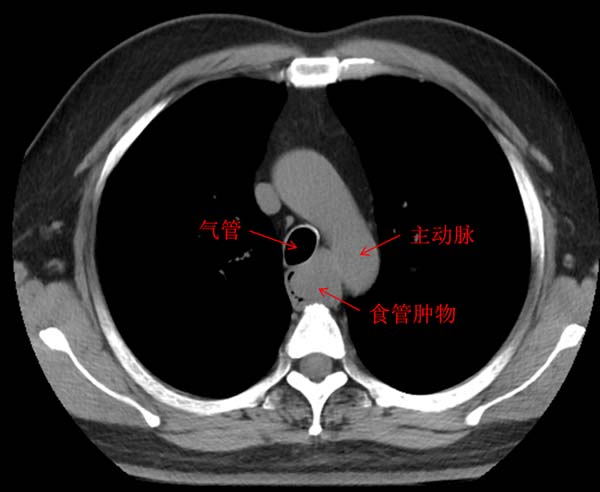

8 个月前,老吕因进食后出现哽噎感,前往北京一家三级医院的消化内科就诊。经过检查一喜一忧两个消息让老吕犯了难。好消息是,内镜下并未呈现出食管癌的典型表现;但坏消息却是,食管上确确实实长了个东西,其表面黏膜光滑,很可能源自黏膜下层。超声内镜和胸部 CT 给出的诊断结果显示肿物肿物大小足有 5 公分,来源于食管固有肌层,平滑肌瘤的可能性较大,但它向内压迫食管管腔,致使食管狭窄,进而造成了进食后的哽噎感症状,向外突出于食管外壁,并且与支气管、主动脉关系紧密。

虽然是个良性瘤,但这个位置,如何治疗却成了棘手难题。因为这个肿物体积庞大,一部分位于食管壁外。若在内镜下治疗,需进行全层切除,这会导致穿孔,而穿孔后消化内镜难以对创面进行有效闭合,形成食管瘘的概率极高。而胸外科医生的顾虑更多,胸腔镜下分离肿物可能损伤食管粘膜层,引发食管瘘,镜下缝合后还存在食管狭窄的风险。特别是肿物位置深,与气管、主动脉相邻,一旦术中伤及这些重要组织,会造成气管瘘甚至大出血。最终老吕辗转多家医院给出的结果是,定期复查,待到 “迫不得已”时再做处理。